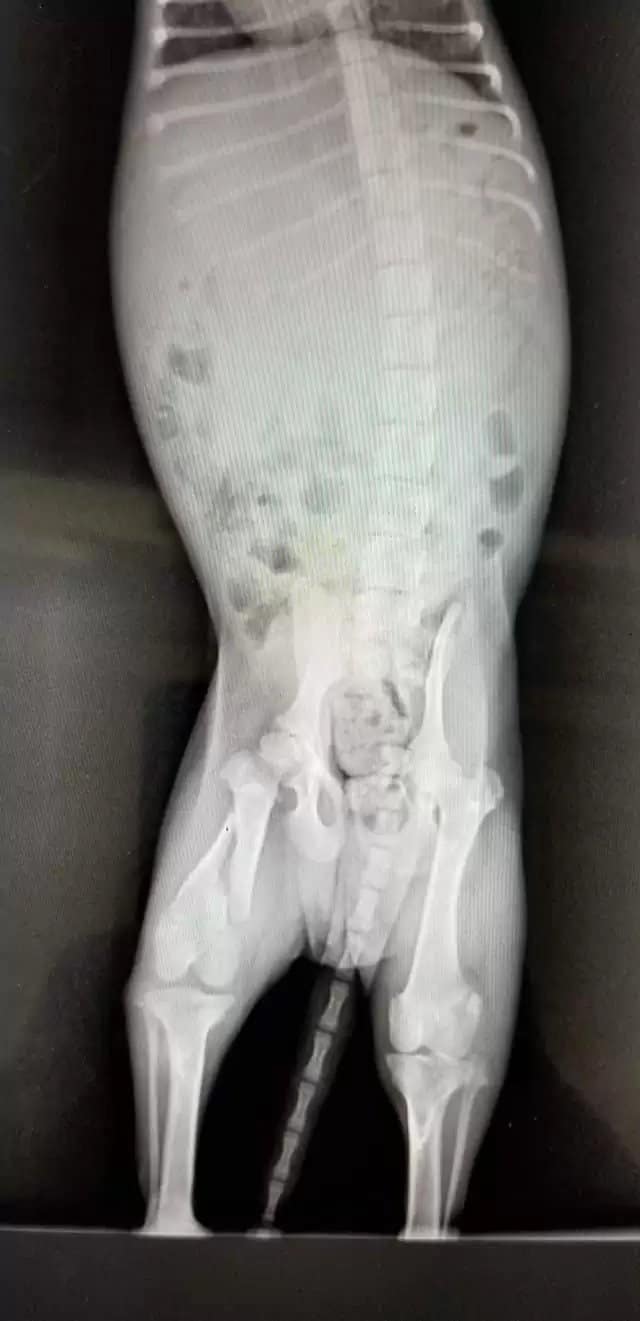

Initially, the vet staff thought they had the situation under control, but further examinations revealed the puppy also had a broken leg, which had been left untreated for too long.

Surgery was the only option.

Given the circumstances and where the dog was found, it was concluded he had been thrown off the bridge, likely landing on hard ground instead of water.

Miraculously, the puppy survived this brutal act, though he was badly injured.